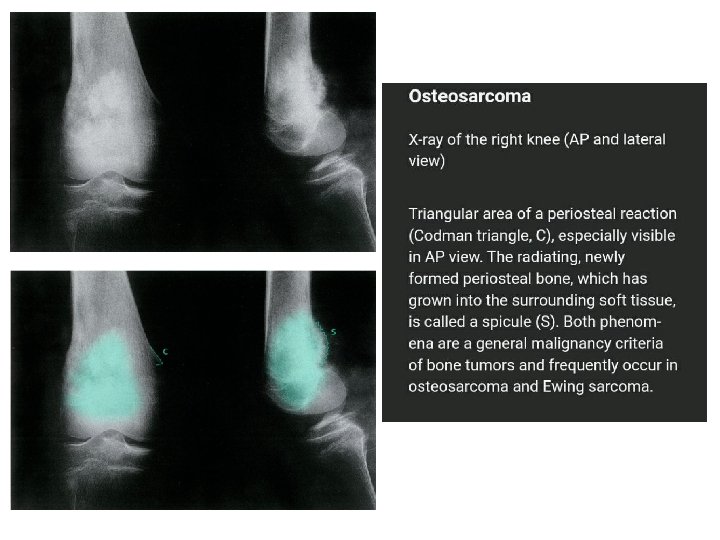

Osteosarcoma Primary osteosarcoma: unknown Secondary osteosarcoma: Paget's disease of bone, radiation injury, bone infarction Incidence: bimodal distribution Primary osteosarcoma: puberty/adolescence Secondary osteosarcoma: advanced age Sex: ♂ > ♀

The sites most commonly involved are the metaphyseal region of long tubular bones, especially the region around knee joint 50% Pain is usually the first symptom; it is constant, worse at night and gradually increases in severity. Sometimes the patient presents with a lump. Pathological fracture is rare. Metastases